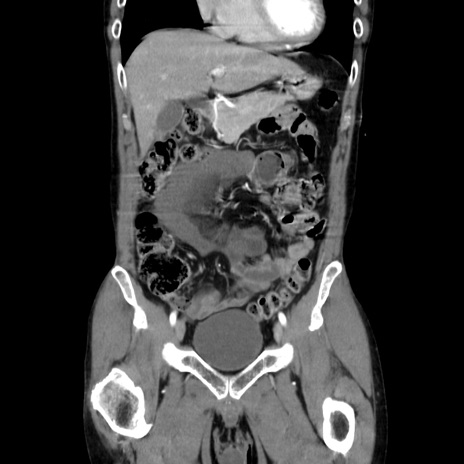

症例37(冠状断像)

【症例】40歳代 男性

【主訴】腹痛

【現病歴】4時間ほど前に電車に乗車中に臍部上より腹痛出現。徐々に増悪し起立困難となり、救急外来受診。生ものは数日食べていない。今朝お雑煮を食べた。

【身体所見】BT 36.8℃、BP 117/84mmHg、HR 91/min、SpO2 97%、苦悶様、腹部:臍上部広範囲圧痛あり、反跳痛±

【データ】WBC 8100、CRP 0.03